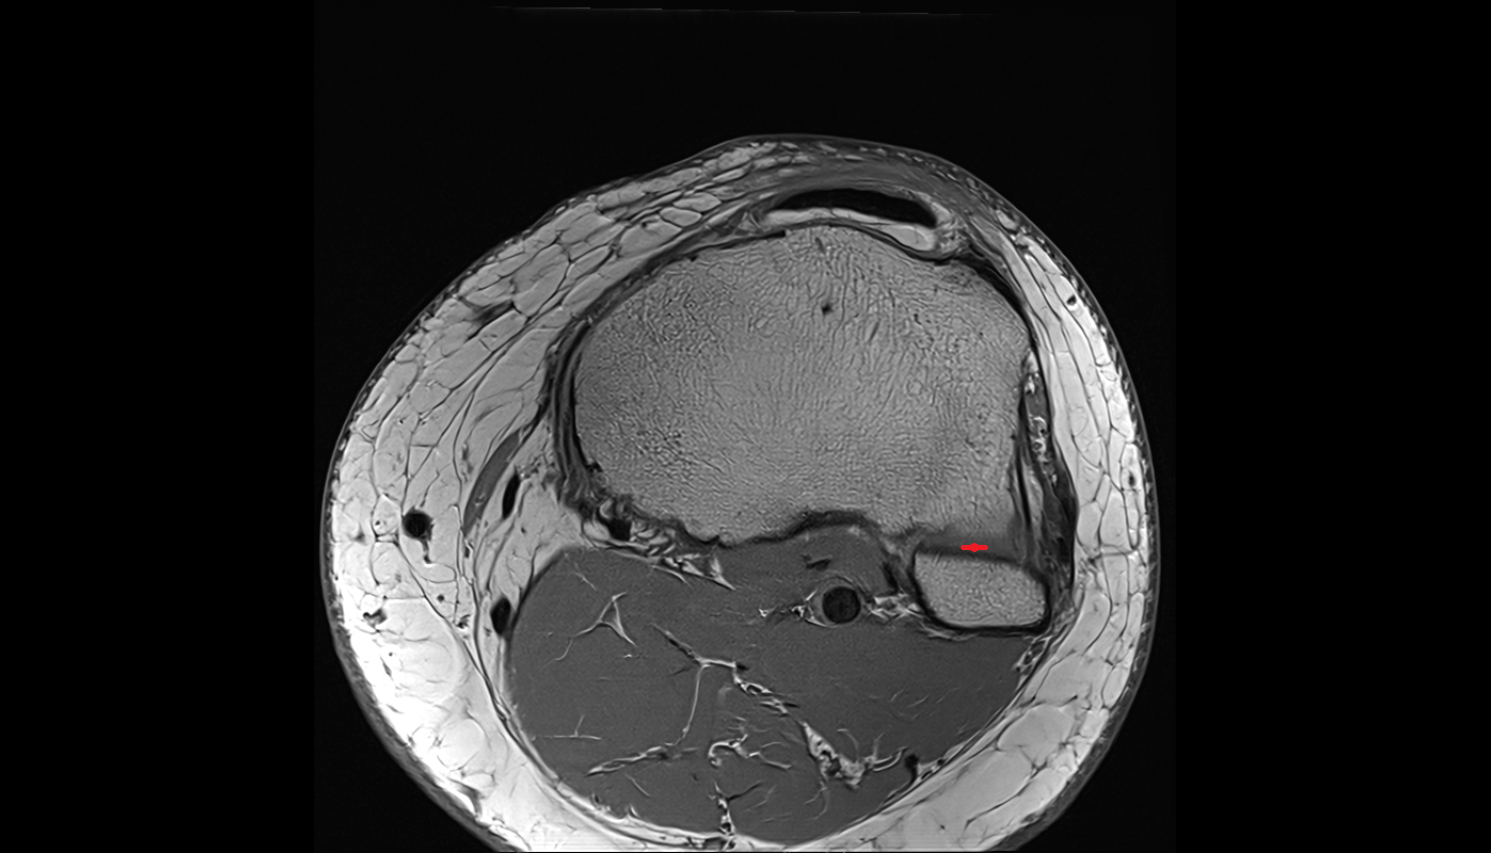

- Anterior cruciate ligament

- Posterior cruciate ligament

- Medial meniscus

- Lateral meniscus

- Anterior horn of lateral meniscus

- Posterior horn of lateral meniscus

- Body of lateral meniscus

- Anterior root of lateral meniscus

- Posterior root of lateral meniscus